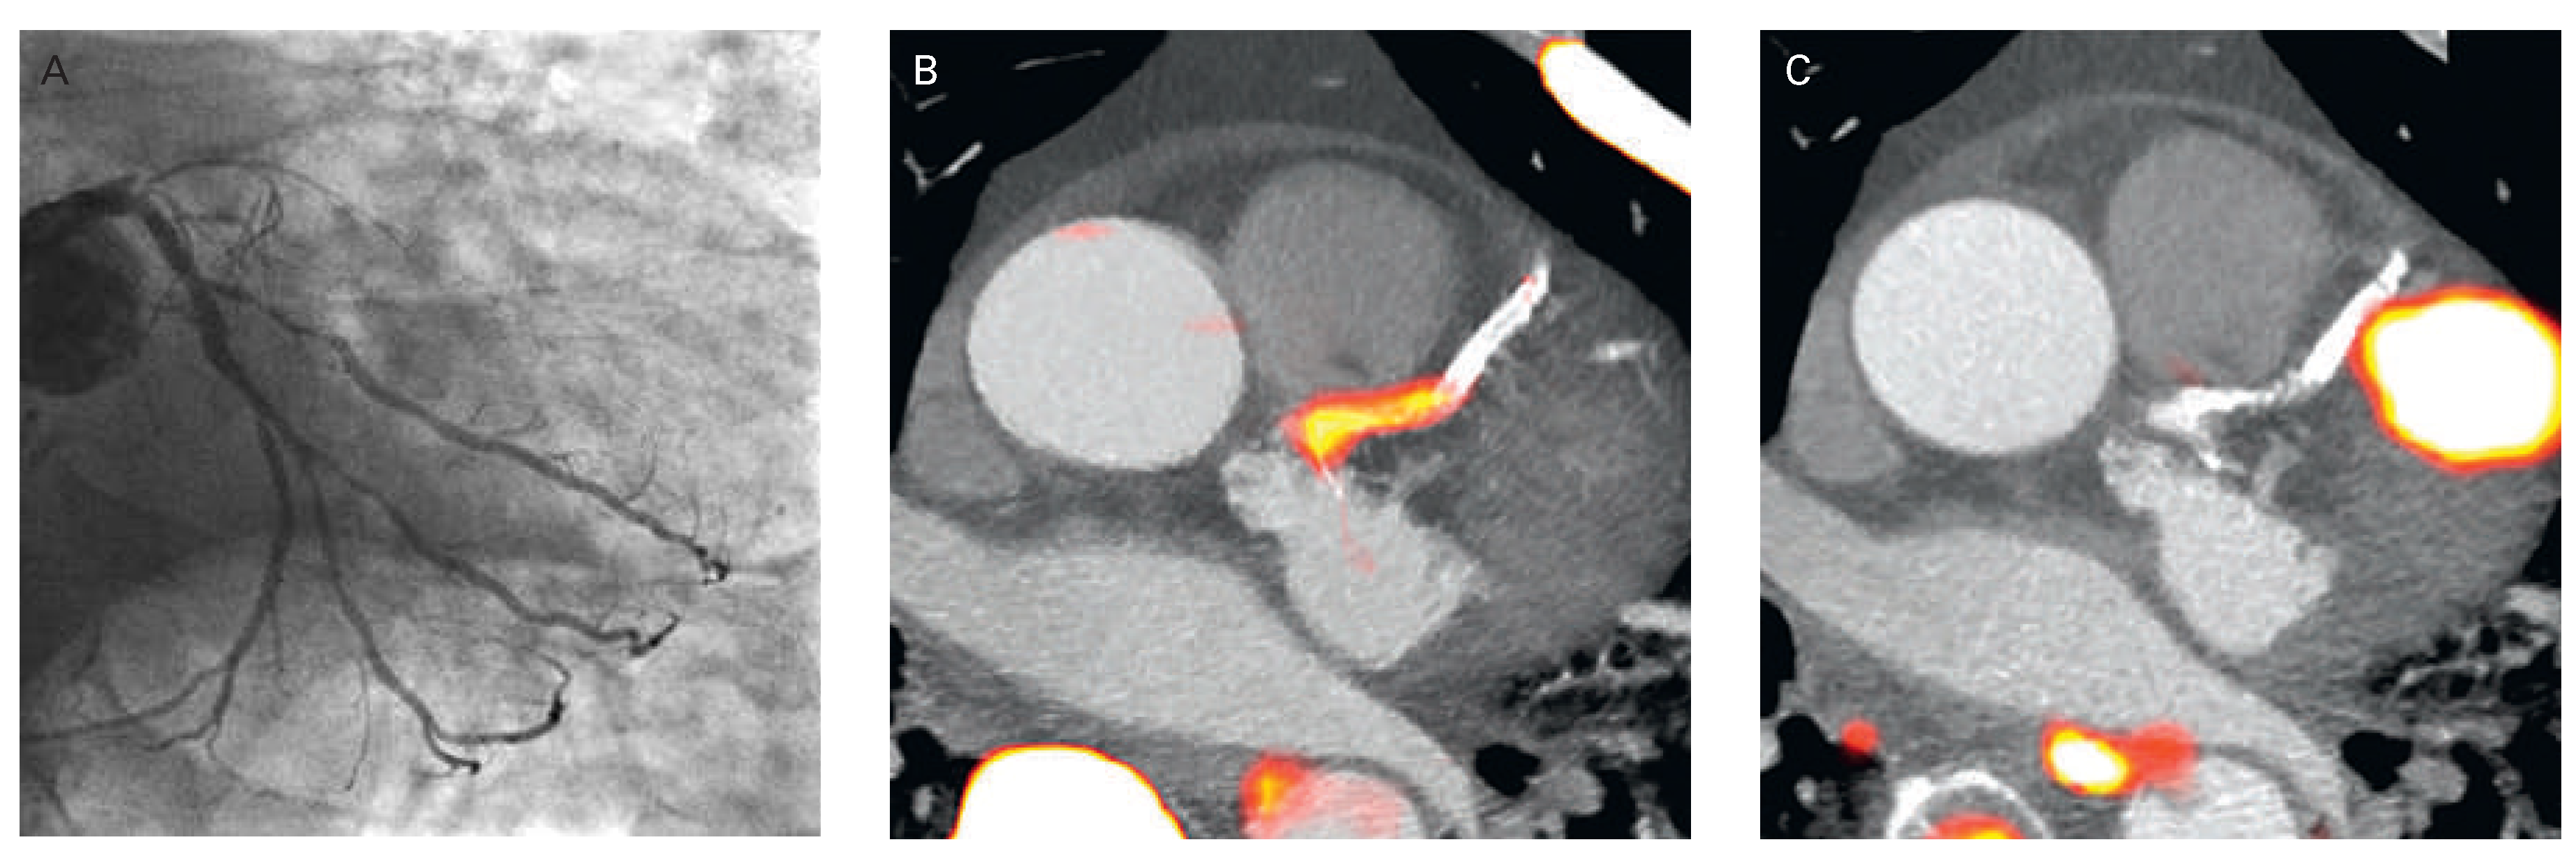

Figure 1. 13N-ammonia PET in the evaluation of multivessel CAD. (A) Myocardial perfusion study with 13N-ammonia PET/CT during dipyridamole stimulation and at rest in a 61-year-old patient with arterial hypertension and type 2 diabetes mellitus. On stress images, there is a moderately decreased perfusion defect involving the mid-to-distal anterior, anteroseptal, and apical regions of the left ventricle, which becomes reversible on the rest images. Uptake is preserved in the lateral and inferior regions. (B) Regional myocardial blood flow quantification (MBF) and myocardial flow reserve (MFR) calculation with 13N-ammonia PET/CT and tracer kinetic modelling. The summarised quantitative data suggest a distinct impairment of the MFR not only in the (LAD) territory, but also in the RCA and LCX vascular territories (regional MFR <2.0). (C) Invasive coronary angiography in this patient demonstrated a proximal occlusion of the LAD, 80% stenosis in the proximal segments of the LCX (left panel), and sequential 50% to 60% lesions in the RCA (right panel). Corresponding regional MFRs are demonstrated for each vascular territory. Reprinted from: Schindler TH, Schelbert HR, Quercioli A, Dilsizian V. Cardiac PET imaging for the detection and monitoring of coronary artery disease and microvascular health. JACC Cardiovasc Imaging. 2010;3:623–40, with permission from Elsevier. (MBF = myocardial blood flow; MFR = myocardial flow reserve; LAD = left anterior descending artery; LCx = left circumflex artery; RCA = right coronary artery.).